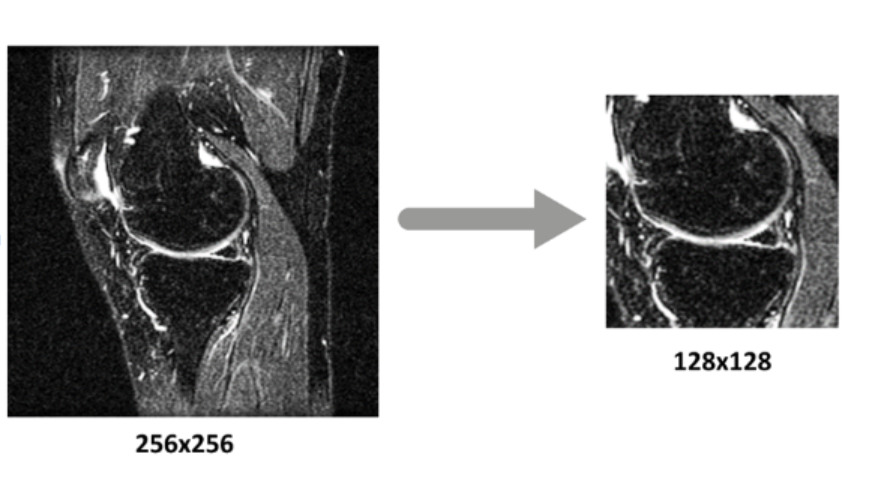

The resizing of the images of the dataset was essential since it allowed for the CNN to focus only on the image of the knee in order to extract information. By isolating and training the neural networks only on that part of the image, a lot of the noise in the dataset was removed and the efficiency of the CNN increased significantly.

Center Cropping

The preprocessing function extracts 128×128 pixel center crops from original 256×256 images, maintaining anatomical focus on the meniscus region and creating an organized folder structure for processed images.

Preprocessing Benefits

- Dimensionality reduction: Faster training with smaller images

- Focus on ROI: Centers on the meniscus area

- Consistency: Uniform input size for the neural network

- MRI images in sagittal plane with original size 256×256 pixels